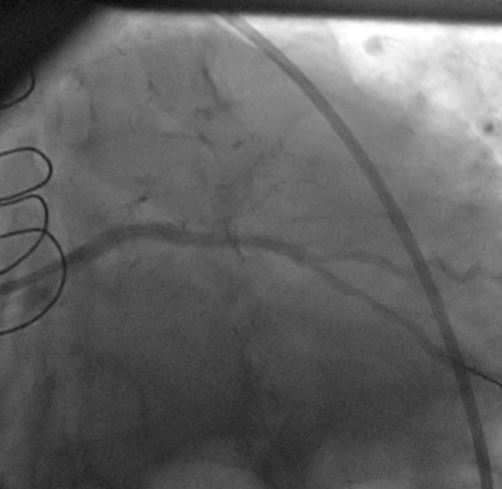

1) LM: subtotal ISR lesion (figure 2, figure 3)

2) LAD: occluded at the ostium and filled via LIMA

3) LCX: proximal non-significant lesion

4) RCA: mild diffuse disease